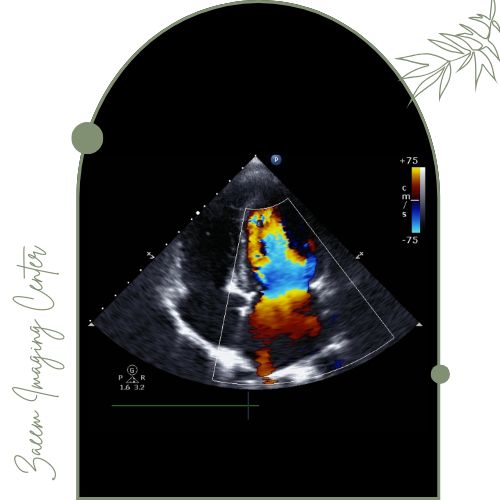

سونوگرافی کالر داپلر

سونوگرافی کالر داپلر یکی از انواع پیشرفته تصویربرداری پزشکی است که بهطور خاص برای بررسی جریان خون در عروق و اندامهای بدن مورد استفاده قرار میگیرد. این روش تلفیقی از سونوگرافی معمولی و تکنیک داپلر رنگی بوده و با ارائه تصاویر زنده و رنگی سرعت و جهت جریان خون را در رگها و شریانها نمایش میدهد. کاربرد اصلی کالر داپلر تشخیص بیماریهای عروقی مانند تنگی یا انسداد عروق، بررسی وریدها و شریانها، ارزیابی سلامت قلب و عروق محیطی و برخی بیماریهای مادرزادی یا اکتسابی است. این تکنولوژی غیرتهاجمی و بیخطر بوده و با دقت بالا به پزشک کمک میکند تا مشکلات گردش خون یا اختلالات عروقی را بهموقع شناسایی و درمان کند.